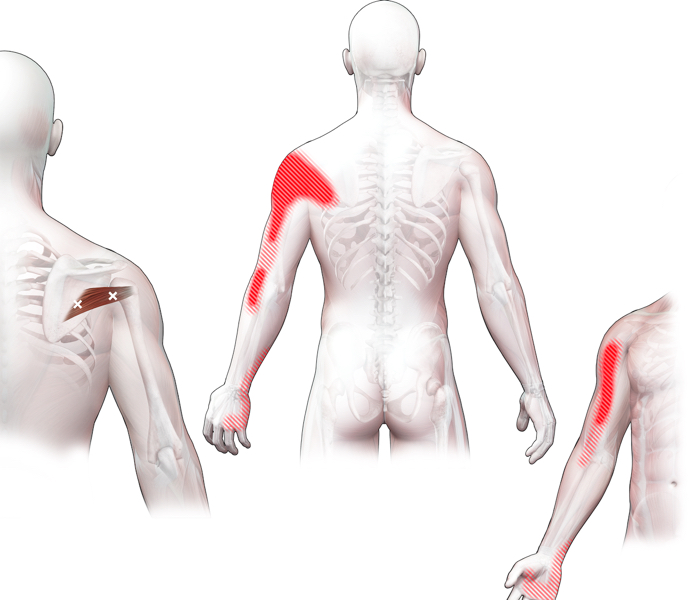

Spieren (Nederlands)

Spieren (nederlands)

Spieren (Latijn)

Spieren (latijn)

Trefwoorden

Trefwoorden